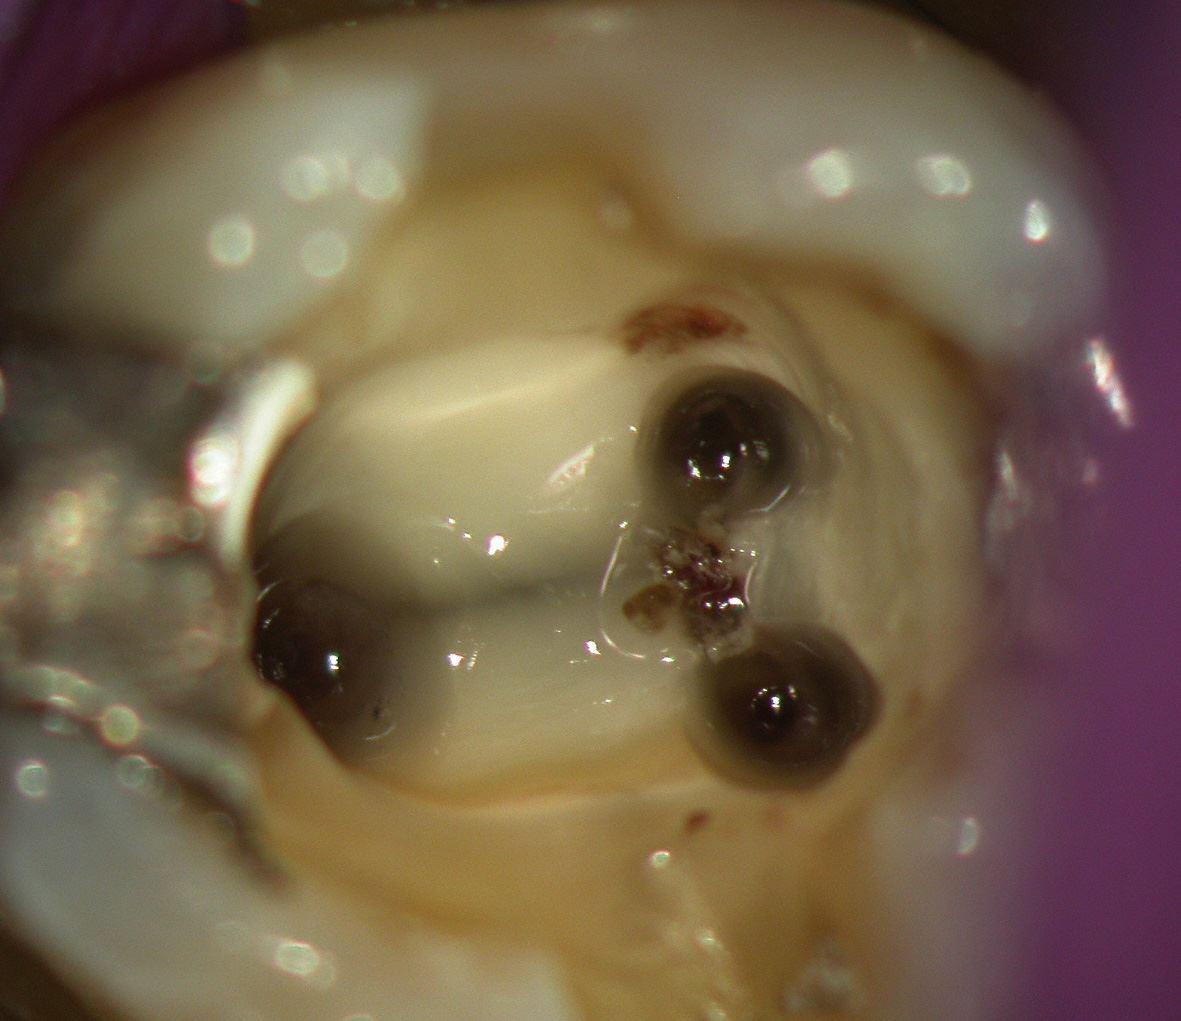

Unter örtlicher Betäubung ist die Behandlung meist schmerzfrei. Nach Entfernung der Karies und nach der Schaffung eines Zugangs in den Zahn werden die Kanaleingänge dargestellt und die Länge jedes einzelnen Kanals wird möglichst exakt unter Anwendung von Röntgen ausgemessen. Abhängig vom zu behandelten Zahn kann die Anzahl der Kanäle stark variieren.

Da die Kanaleingänge oft sehr eng sind, werden meistens eine stark vergrößernde Lupenbrille oder ein Operationsmikroskop verwendet.